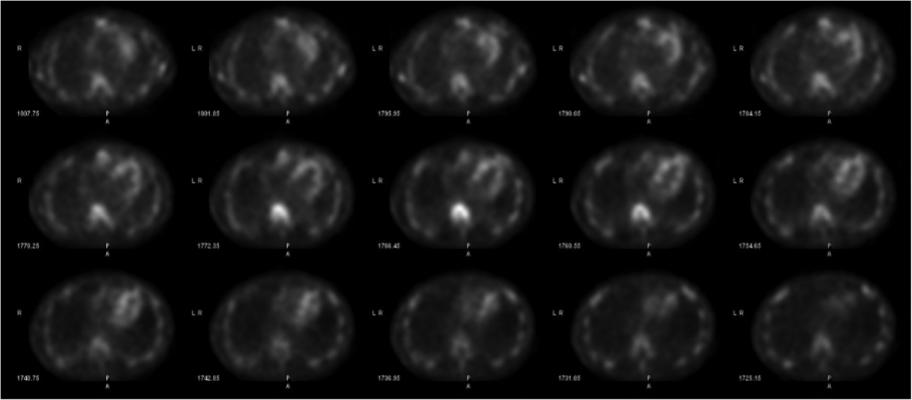

Cardiac amyloidosis is emerging as an underdiagnosed cause of heart failure and mortality characterized by the deposition of amyloid fibrils (misfolded protein deposits) into myocardial tissue. An ideal non-invasive diagnostic method would identify cardiac involvement in amyloidosis and would also confirm the etiologic subtype. No existing diagnostic tools can provide this information individually, necessitating a multimodality cardiac imaging approach.